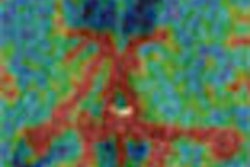

A series of five contrast-enhanced MR images were acquired, starting at zero minutes after injection and then again at two, four, six, and eight minutes. Coronal and transverse maximum intensity projections (MIPs) were prepared from the subtracted MR images. Scores ranging from 0-3 (absent or very low breast vascularity to high breast vascularity) were assigned to the MIP images. The 72 patients who underwent gadobenate dimeglumine MR were imaged again two months later.

The mean score assigned to the vascularity map obtained with 0.05 mmol/kg of gadobenate dimeglumine MR was 1.9; for the map acquired with 0.1 mmol/kg, the mean score was 1.07; and 2.0 when the dose was raised to 0.2 mmol/kg. These scores were significantly higher than those assigned to the gadopentetate dimeglumine MR images (mean of 1.24), the authors stated.

"Asymmetric breast vascularity due to the presence of one-sided increased vascularity was observed in 47 of 67 patients examined with gadobenate dimeglumine-enhanced MR imaging. In 44 (94%) of these 47 patients, the increased vascularity was associated with histopathologically proved ipsilateral breast cancer," the authors reported.

"Our experience revealed that MR imaging with gadobenate dimeglumine administered at doses as low as 0.05 mmol/kg enables high-quality vascular maps of the breast," they wrote. "Our findings also suggest that vascular map asymmetry may be a finding that is frequently associated with ipsilateral invasive breast cancer."